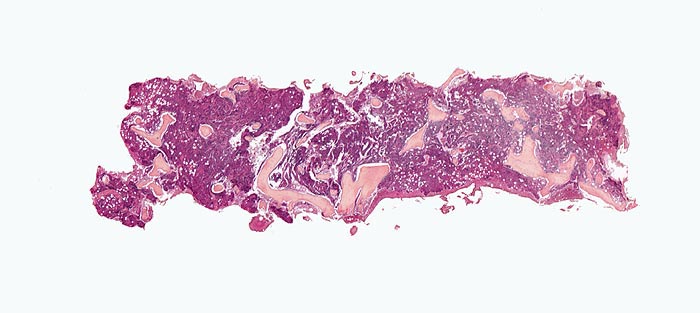

Primäre Myelofibrose (PMF)

Knochenmark, Beckenkamm

Hyperplastisches Mark mit wechselnder Verdrängung des Fettmarks. Die Spongiosabälkchen sind diskret verplumt und verdickt.

Splenomegalie, leichte Anämie, Leukozytose und Thrombozytose festgestellt bei einer Routineuntersuchung bei asymptomatischer Patientin.